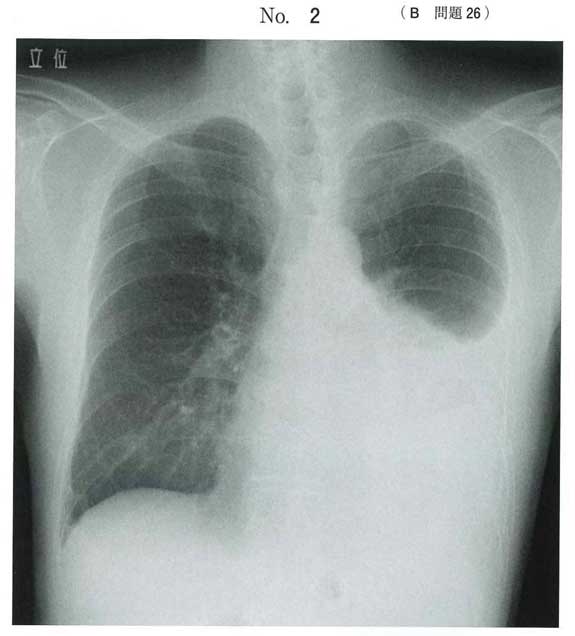

b)

胸膜炎で胸水貯留

b:胸膜炎

胸膜炎では、胸水で肺が圧迫されることによる息切れや呼吸困難、胸膜への刺激による空咳や痰、ピリピリとした鋭い胸痛、胸部の違和感や圧迫感などの症状が現れます(胸膜痛)。特に深呼吸や咳をした時に強くなり、人によっては背中に痛みを感じることもあります。強い痛みが生じるのは、壁側胸膜に「知覚神経」という痛みを伝える神経が豊富に通っているためです。

bです。